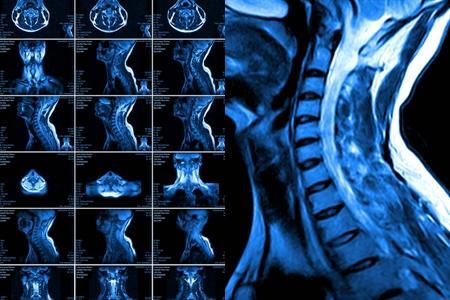

头晕,头晕,是得了颈椎病?一分钟自测,认识颈椎病原来这么简单

颈椎病对于很多人来说不陌生,但是传统意识中,大部分人认为颈椎病就是脖子疼。专家提醒,其实颈椎病症状多样,可体现在全身多个位置,了解后对于及时发现病情专业治疗有直接的帮助。

如何判断是否患有颈椎病?